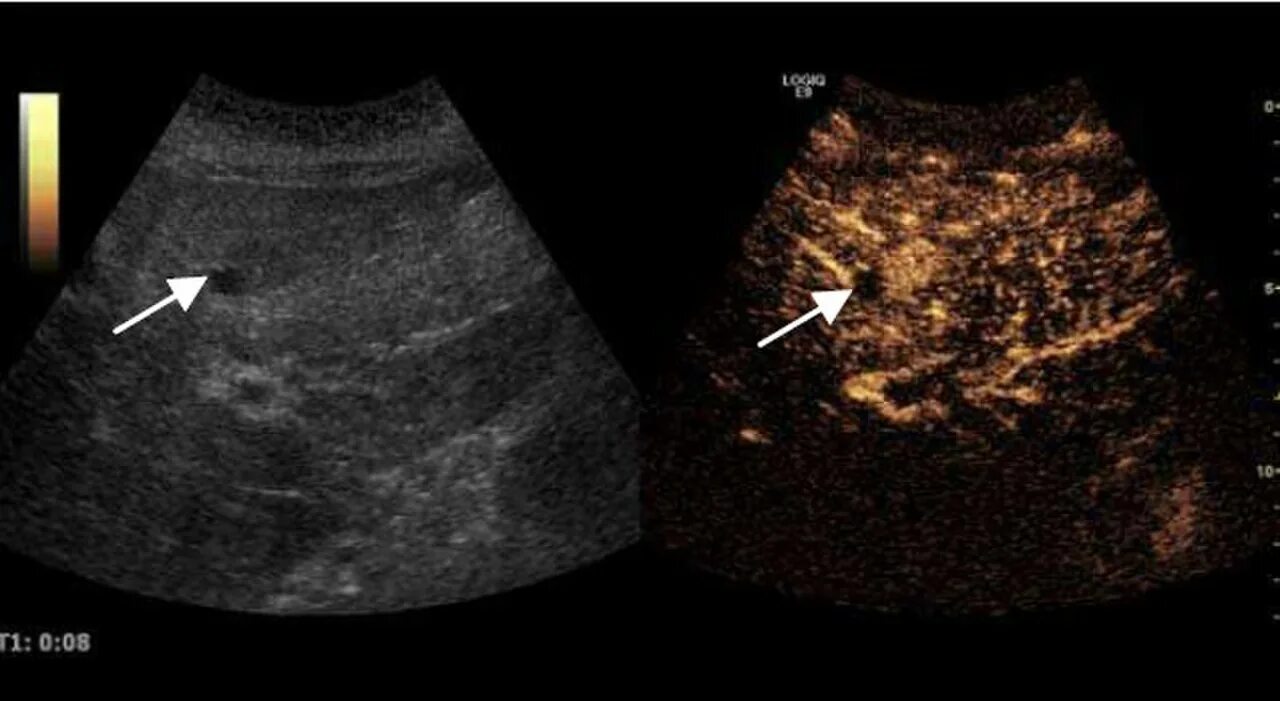

Метастазы в печени на узи как выглядят